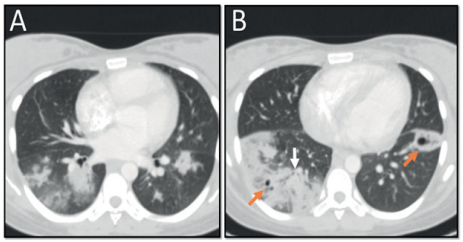

Mujer de 24 años de raza mestiza, procedente del municipio de Soledad, Atlántico, quien se dedica a labores del hogar. Consulta de urgencias por cuatro semanas de evolución con fiebre de patrón intermitente, asociado a tos húmeda con expectoración purulenta, dolor pleurítico derecho y disnea de esfuerzo que progresa hasta el reposo. Antecedentes de puerperio tardío de 37 días por parto vaginal (28/08/2019), con producto a término, con peso adecuado al nacer sin complicaciones. Cinco días previos a la consulta estuvo hospitalizada por la misma sintomatología actual y recibió terapia antimicrobiana parenteral; sin embargo, solicitó el retiro voluntario de dicha institución. Ingresó a una clínica de la ciudad de Barranquilla, con taquicardia, taquipnea y temperatura de 38,9 °C. En la exploración física se halló hipoventilación en bases pulmonares, crépitos generalizados con predominio basal derecho y sibilancias espiratorias ocasionales. En la analítica sanguínea presentó hemograma con leucocitosis y neutrofilia, anemia grado 3 OMS y elevación de reactantes de fase aguda (leucocitos: 22.090 x103/mm3, neutrófilos: 88,4 %, hemoglobina: 6,6 gr/dl, VCM: 81,7 dL., HCM: 26,3 pg., plaquetas: 188.000 x103/mm3, proteína C reactiva cuantitativa: 314 mg/L, VSG: 100 mm/hora, creatinina: 0,53 mg/dl), radiografía de tórax (figura 1). Con consolidado basal derecho y opacidades alveolares con distribución multilobar de predominio en hemitórax izquierdo, TC de tórax (figura 2). Con áreas de consolidación en base derecha, nódulos múltiples con distribución predominante peribroncovascular, algunos de ellos cavitados, adenopatías mediastinales. Se inició tratamiento antimicrobiano con piperacilina tazobactam más claritromicina y transfusión de hemoderivados y estudios de extensión. La valora el Servicio de Neumología, que en el diagnóstico diferencial considera neumonía bacteriana, micosis, micobacterias, enfermedades granulomatosas y malignidad. Los exámenes de control documentaron baciloscopia seriada. No se observan BAAR en 100 campos microscópicos. Anticuerpos para VIH: egativo, anticuerpos antinucleares: negativo, P-ANCA: negativo, C-ANCA negativo, complemento C3: 100 mg/dl (normal), complemento C4: 12 mg/dl (normal), gases de arteriales sin alteración del ácido base o trastorno de la oxigenación. PCR para Mycobacterium Tuberculosis (GeneXpert MYB-RIF) en muestra de esputo: negativo, hemocultivos negativos a los cinco días de incubación. TC de senos paranasales: normal. Por presentar deterioro clínico requirió ingreso a la Unidad de Cuidados Intensivos. Se inicia terapia tetraconjugada con RHZE por sospecha para Mycobacterium tuberculosis y se escalona terapia antimicrobiana con meropenem y vancomicina. El departamento de Cirugía del Tórax realiza videotoracoscopia en la que encuentra el pulmón atrapado. Se realiza decorticación pulmonar liberando el pulmón y lobectomía segmentaria del lóbulo inferior derecho. Se envía una muestra para estudio histopatológico. Después del control de fuente y el manejo antimicrobiano, la paciente mejora su patrón respiratorio y se le da la alta médica, con la recomendación de continuar el tratamiento antituberculoso. El estudio histopatológico del espécimen de segmento pulmonar del LID documenta inflamación aguda y crónica severa, mediado por linfocitos y leucocitos polimorfonucleares, áreas de necrosis y formación de absceso, estudio negativo para granulomas o cambios malignos, aislamiento de Staphylococcus Aureus. Finalmente, se suspende el tratamiento tetraconjugado.

Radiografía de Tórax en proyección PA